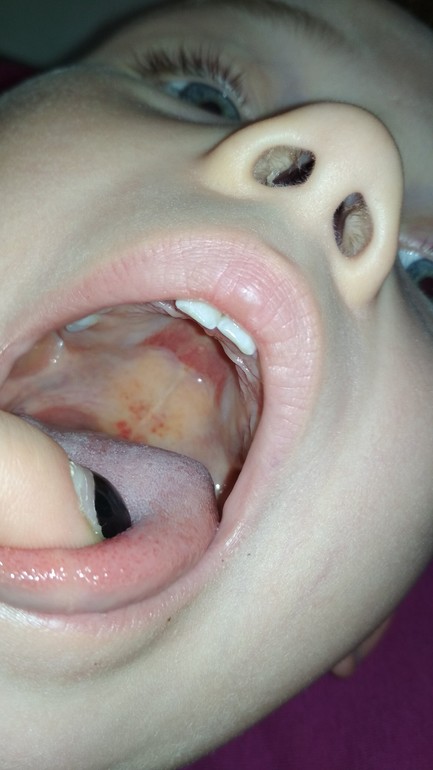

Здравствуйте! Я к вам за мнением. Расскажу по порядку. С начала марта у Ярика появилась температура 36.8-37.5, на нёбе были кровоподтеки. Сдали кровь (прилагаю, от 13 марта). Педиатр смотрел - ничего не нашёл, сказал в анализах вялотекущая инфекция. Назначил пересдать кровь и сдать мочу именно в поликлинике (прилагаю, от 19.03).Фото горла также прилагаю (где не пятна, а излияния. Вопрос: что видите вы по анализам с учетом симптомов?

2. 15 апреля Ярик пожаловался на то, что больно глотать (фото горла прикладываю, фото на второй день болезни), на третий день - высыпания на спине, на четвертый день - по всему телу. Сыпь, как мурашки, розоватые. Сыпь прошла через 7 дней. Мазок и кровь в начале не назначили. Поставили скарлатину. Пили антибиотик и симптоматически лечили горло. Анализы прилагаю на 12 день болезни и еще через неделю (гемотест от 24 апреля и кдл от 02 мая). Кожа не облазила. Диагноз поставила заведующая на дому, далее нас наблюдал педиатр и лор - они оба выразили сомнение в диагнозе и удивление, что не взяли мазок и это мог быть мононуклеоз. Вопрос: что видите вы по анализам и клин.картине?